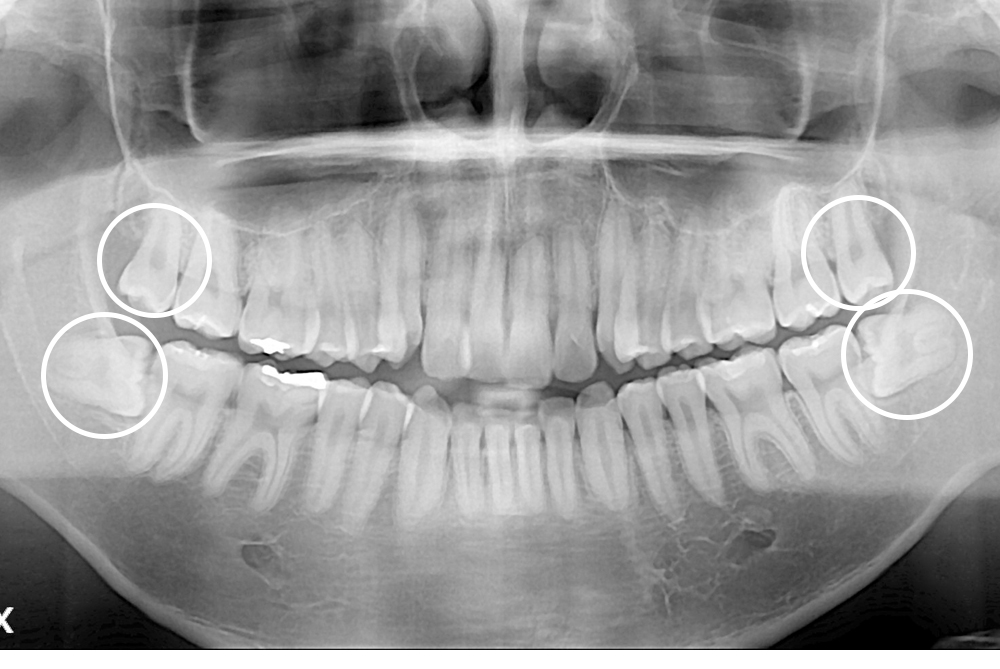

[사랑니] 매복 사랑니 발치

치료후 : 2018-03-26

세종치과는 구강악안면외과학 박사이신 원장님이 발치하는 치과입니다.